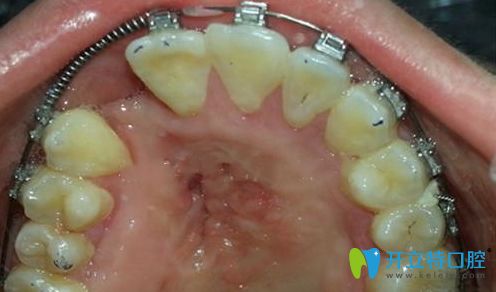

唇腭裂做牙齒矯正的圖片

唇腭裂會(huì)引起哪些牙齒問(wèn)題呢?

先天性唇腭裂,有些除了嘴唇鼻子的畸形和軟硬腭的裂開(kāi)以外呢,也會(huì)存在著牙齒的畸形。而唇腭裂又常會(huì)引起牙齒的畸形、牙齒的扭轉(zhuǎn)、牙齒位置排列異常,就要采用正畸的治療方法。